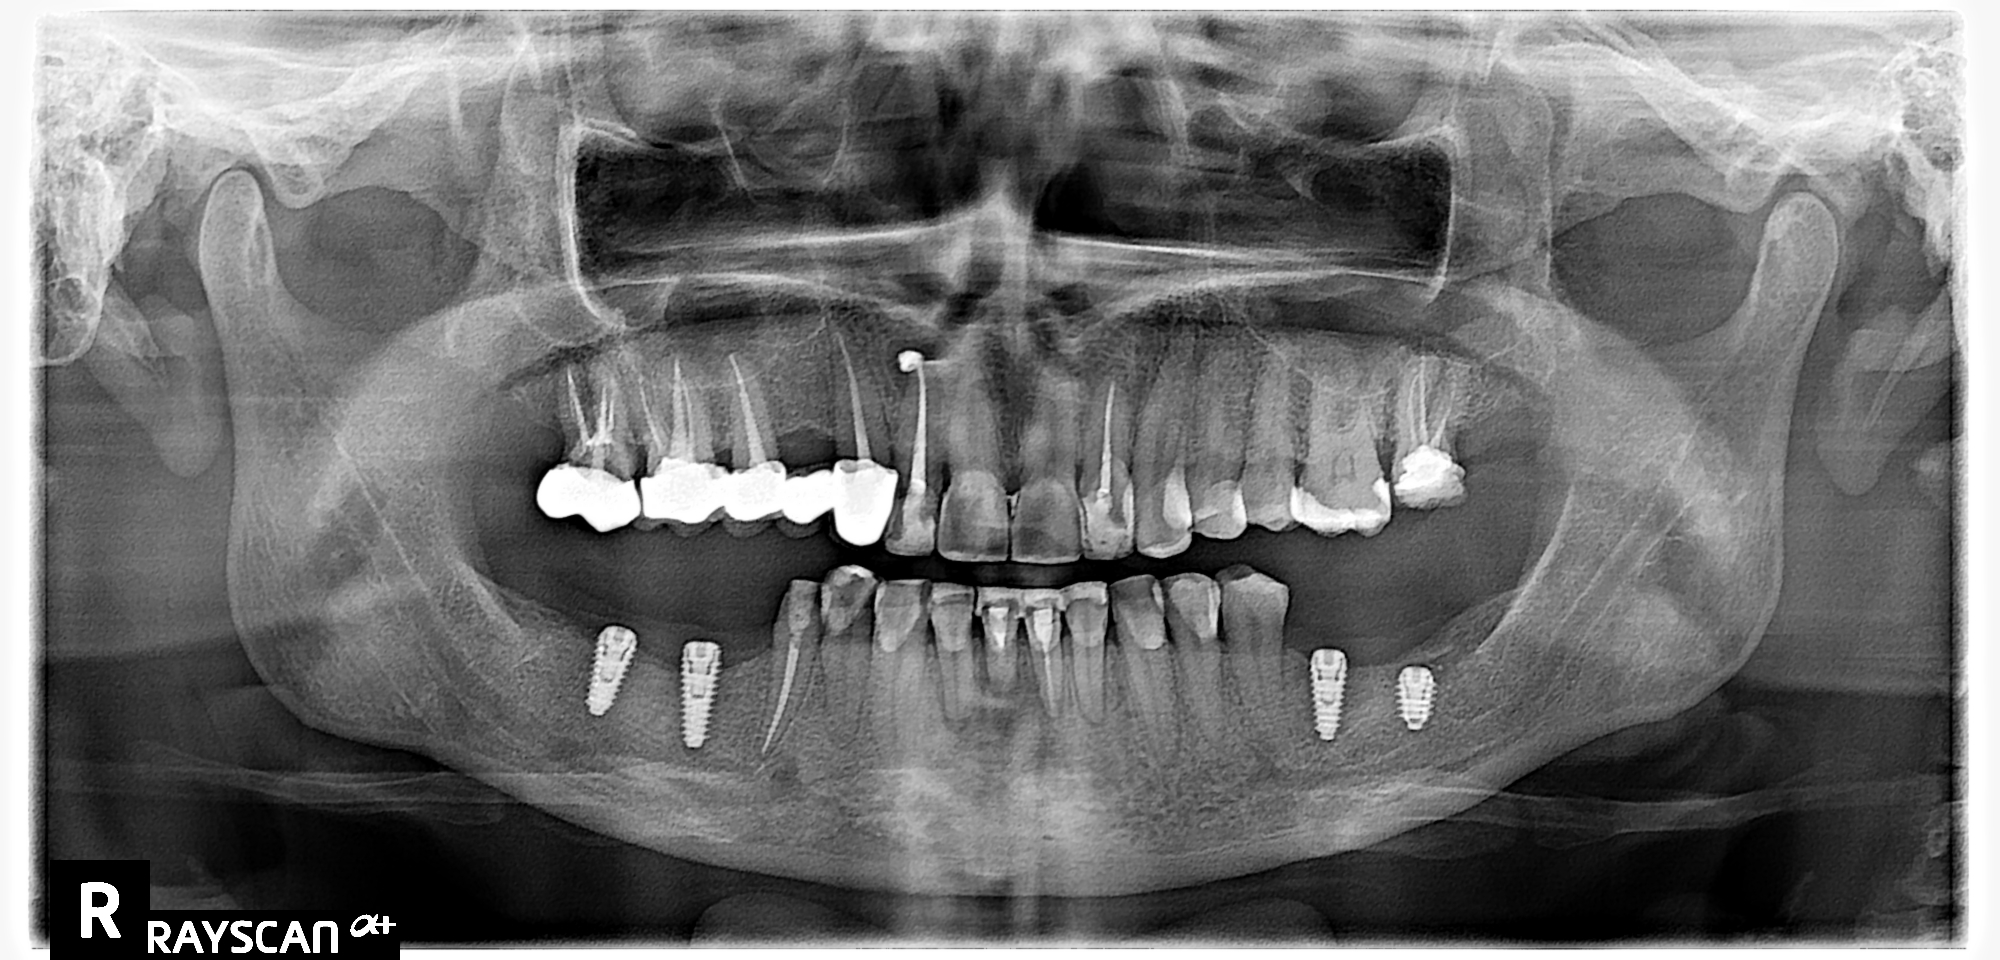

Протезирование

- 3Д компьютерное обследование (проверка приживления имплантов)

- установка формирователей десны

- изготовление 4 абатментов на импланты

- изготовление 13 металлокерамических коронок на жевательные зубы

- изготовление 10 коронок высокой эстетики из диоксида циркона

Фото после окончания лечения

Лечение закончено!